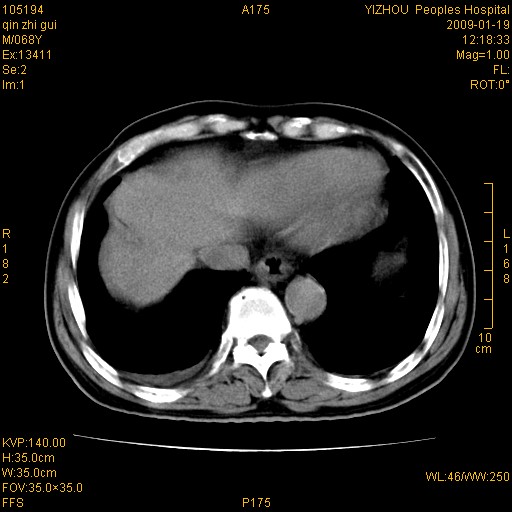

以下是引用随光逐影在2009-1-21 16:11:00的发言:[br]1)考虑肝右叶肝癌并肝静脉及门静脉瘤栓形成。2)肝硬化,少量腹水。3)胆囊炎。4)右侧少量胸腔积液。

病灶外缘凹凸不平,平扫低密度,增强动脉期有强化,门脉早显,静脉期及延期呈延迟强化,结合病史考虑右肝前叶巨块型肝癌可能性大,强化表现不除外胆管细胞癌